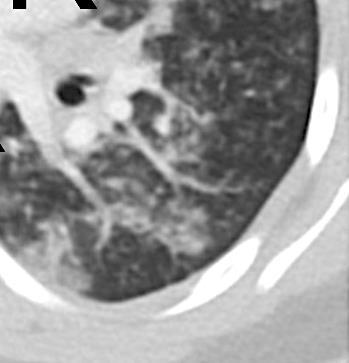

Acute Pediatric COVID-19: CT

21 Imaging of Covid 19 infection in children

3 Phases

Early: "Halo" sign

Local infection

Progressive: Diffuse GGO

Developed: Consolidation

Surr vasc congestion

Inflammation - adj alveoli

Alveoli fill with fluid/cells

Local infection Surr vasc congestion